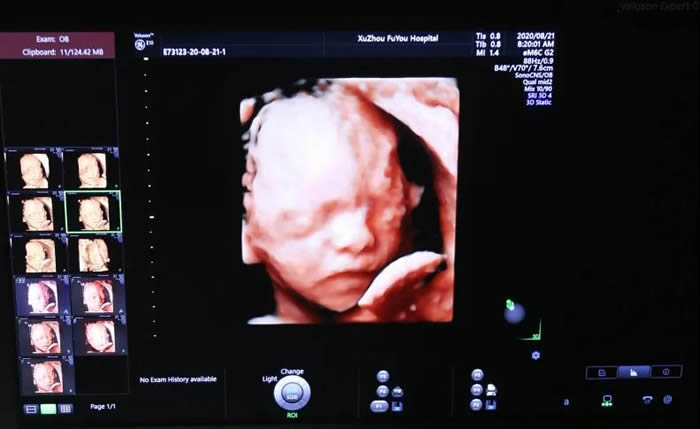

懷胎十月,產(chǎn)檢是一項(xiàng)重要內(nèi)容。隨著四維彩超的普及和商業(yè)的大肆宣傳,有些準(zhǔn)媽媽對(duì)超聲檢查的關(guān)注點(diǎn)也從“醫(yī)學(xué)篩查”變?yōu)樘殞毜?ldquo;面部寫真”,一味追求高清和逼真!

張麗主任介紹,無論是三維還是四維,都是在二維超聲的基礎(chǔ)上,利用計(jì)算機(jī)再處理技術(shù)達(dá)到立體模式重建的超聲診斷技術(shù),能看到胎兒的立體圖形。“也就是說,三維彩超好比照相機(jī),能捕捉胎兒立體靜態(tài)的畫面,四維彩超就像攝像機(jī),可以看到實(shí)時(shí)動(dòng)態(tài)的胎兒畫面,比如:打呵欠、手舞足蹈的過程。”

張主任還有些無奈的提到,有些孕婦一進(jìn)診室就會(huì)詢問,儀器是不是某品牌的?是標(biāo)清還是高清?就像被商業(yè)廣告洗腦一樣,導(dǎo)致大家的關(guān)注點(diǎn)集中在了寶寶的肢體動(dòng)作、顏面部錄像上。

“這是一個(gè)很大的誤區(qū)。超聲科醫(yī)生要做的是在胎兒結(jié)構(gòu)篩查清楚的前提下,擁有一張清楚的面部畫面,這是最完美的。但是,不建議為了捕捉胎兒的一個(gè)動(dòng)作、某個(gè)畫面反復(fù)長(zhǎng)時(shí)間使用。”